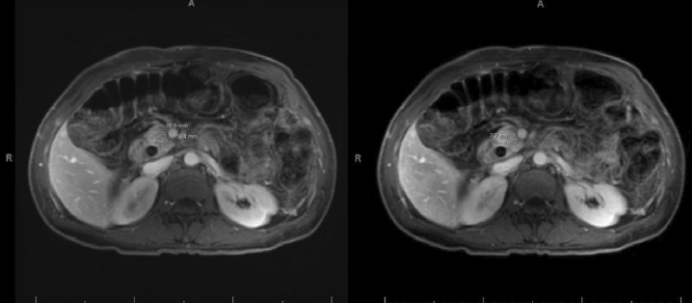

化疗末行 MRI 重新分期,显示胰头肿物缩小,大小 1.9 cm×1.6 cm,包绕部分肠系膜上静脉,胆道积气(图 3)。完成 12 周期化疗后,盆腹腔 CT 显示和 MRI 类似的结果。

图 3. 化疗末 MRI 再分期显示胰头肿物缩小  [1]